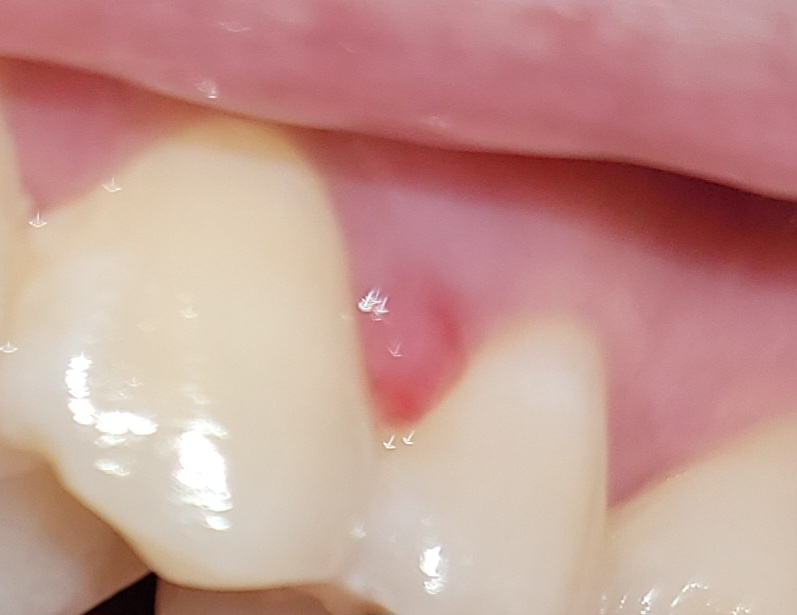

사진으로 봤을 때는 잇몸에 염증이 있는 것으로 보입니다. 해당 부위를 꼼꼼하게 양치질을 해 주시고 치실 씨를 사용해보세요. 그래도 염증이 지속된다면 잇몸 내부의 치석이 있을 수 있기 때문에 이런 경우에는 치석을 제거해 주는 것이 좋습니다.

단순히 양치 칫솔에 의한 잇몸 외상이라면 1~2주 이내에 증상이 완화되고 잇몸이 회복됩니다. 다만 잇몸 질환으로 인하여 해당 부위가 나타났다면 잇몸 치료를 해야 증상이 호전될 수 있습니다.

양치할 때 생긴 상처에 의한 것으로 보이며 자연치유 될 것 같습니다.

일주일 정도 지켜보고 안사라진다면 치과 가보시는 게 좋겠습니다.

단순염증이신거 같은데 시간이 지나도 사라지지 않으면 치과에 가셔서 잇몸치료를 받으셔야될것같습니다.

임상사진 상 볼 때, 시간이 지나면 자연치유 될 것으로 보입니다. 손으로 자주 건들여보는 행동은 감염을 일으킬 수 있으니 피하시고, 혹시 증상이 심해진다면 치과 내원해보세요.

현재 잇몸에 치주낭종이 생긴 것으로 보이며, 이 경우 잇몸에 염증이 있는 것으로 치과치료가 필요로 됩니다. 치석이 쌓여있는 경우 잇몸을 자극하여 염증을 유발하여 발생할수 있기에 스케일링 및 잇몸 치료가 필요로 됩니다.